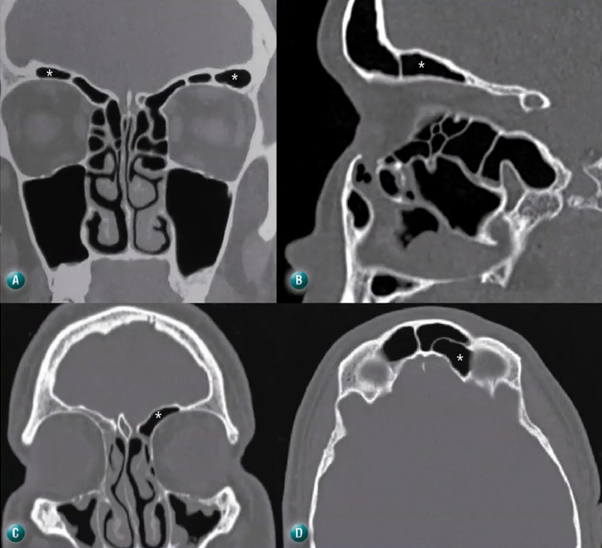

Cite o conceito de que é recesso terminal.

É um fundo cego (asterisco na imagem) formado pela inserção do PU na lâmina papirácea (situação mais prevalente). A drenagem do frontal se dá no meato médio.